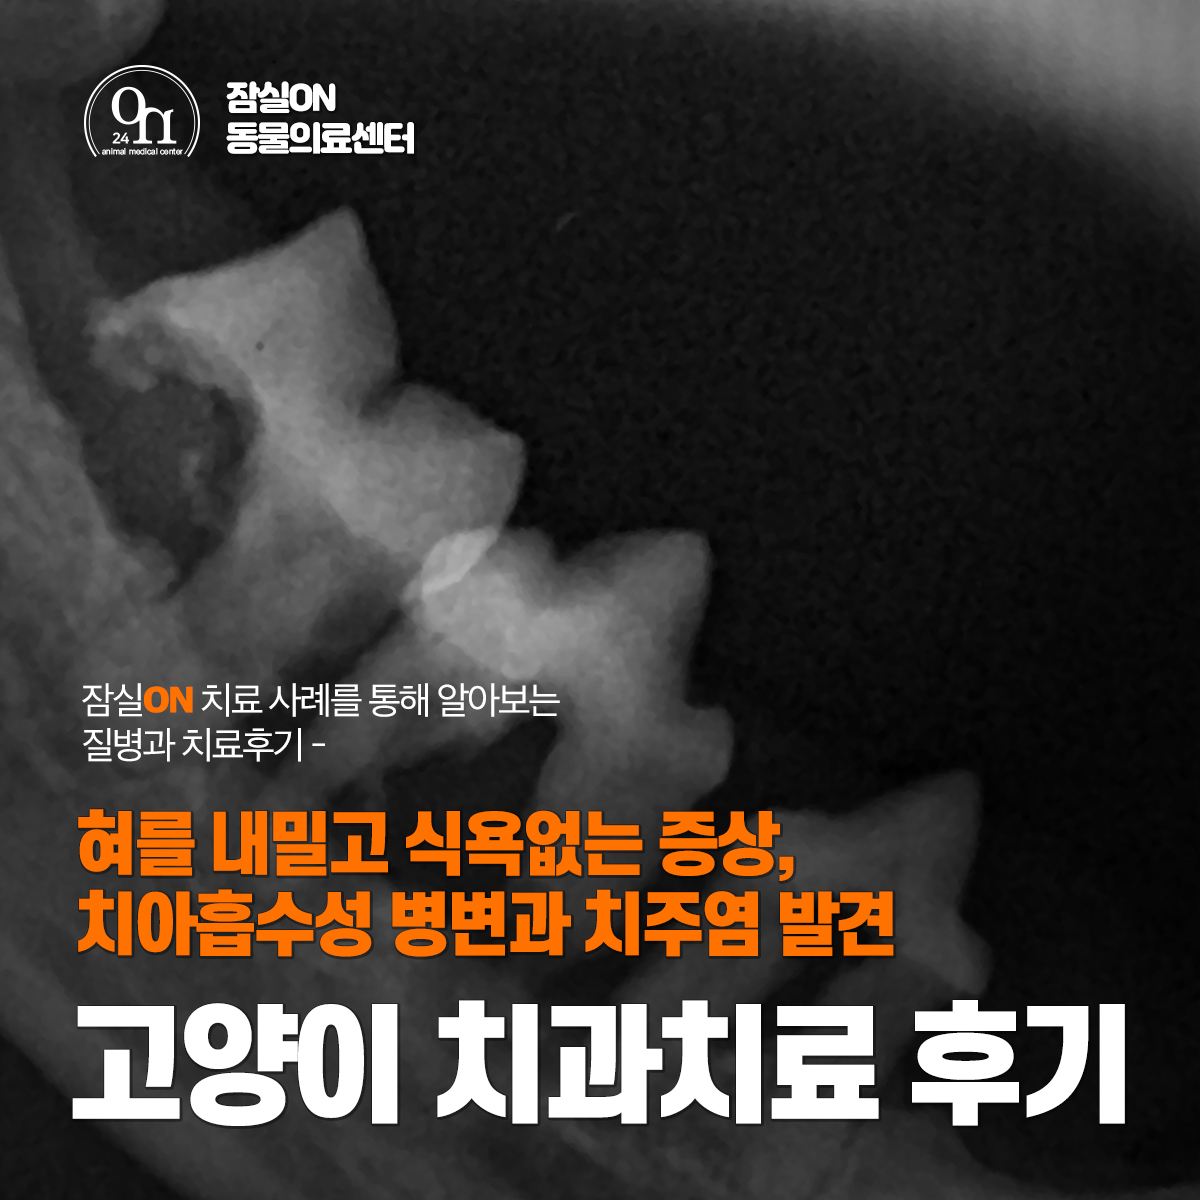

조금 더 정확한 치아 상태를 알기 위해 치과 방사선 촬영을 진행했고 치아 뿌리까지 확인을 했습니다.

치과방사선 촬영 결과 일부 치아는 이미 뿌리가 녹아 있었고 치주골이 녹아내려 뿌리가 드러나 있는 치아들이 확인되었어요. 그리고 치아 흡수성 병변과 치주염이 같이 확인되었답니다.